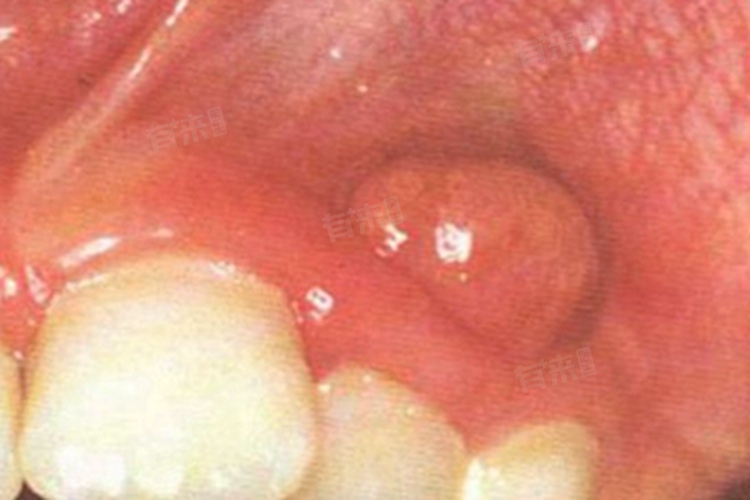

3、牙龈瘤:

- 牙龈瘤的病因尚不十分明确,可能与局部刺激因素有关,如牙结石、不良修复体等,也可能与内分泌因素有关,在女性怀孕期间,由于体内激素水平的变化,更容易发生牙龈瘤。牙龈瘤通常呈圆形或椭圆形,大小不一,有的有蒂,有的无蒂,生长缓慢,一般无明显疼痛。肿块质地较软或中等硬度,颜色与正常牙龈相似或稍红。